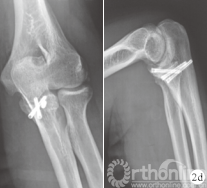

图 2 患者,男,23 岁,左侧尺骨冠状突骨折(Ⅱ型)

d.术后1年肘关节正侧位 X 线片